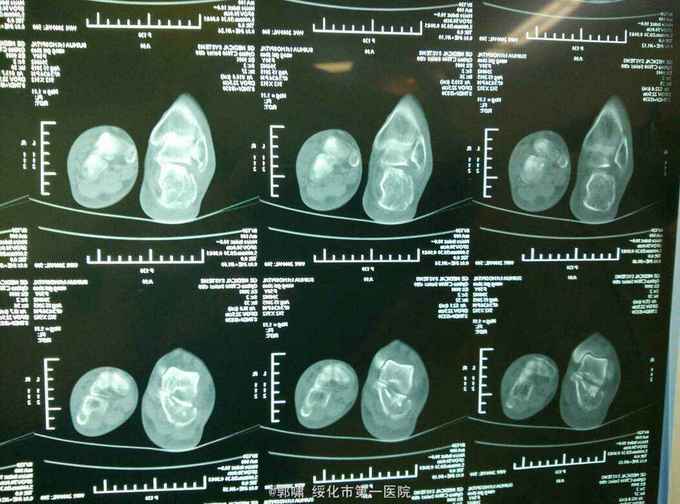

患者老年男性。76岁。自三米高处坠地。右侧跟骨肿胀痛,畸形,活动受限一小时。收入院。病人一小时前不慎自三米高处跌下,当即右足跟局部肿胀,疼痛,畸形。不能行走。立即来诊,门诊拍片示。右侧跟骨粉碎性骨折。收入院。

右侧足跟局部肿胀。足弓消失。局部皮下淤血。压痛。活动受限。不能行走。拍片示。右侧跟骨粉碎性骨折。

诊断。右跟骨粉碎性骨折。病人入院后常规检查。急诊腰麻下闭合复位。横向挤压恢复跟骨横径。克氏针撬拨恢复跟骨贝雷氏角。恢复跟骨关节面平整。沿跟骨长轴交叉传入细克氏针。拧入空心钉。